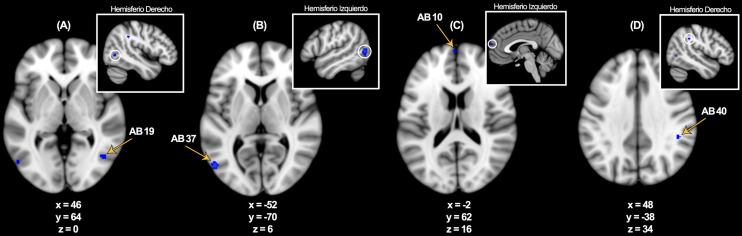

Methods: A meta-analysis was conducted using peer-reviewed, event-related fMRI studies. The Activation Likelihood Estimation (ALE) method was applied via GingerALE software to compare brain activations associated with the encoding of affective visual stimuli presented as either words or photographs. Three contrasts were assessed: pictures > neutral + control, words > neutral + control, and overlap between both.

Results: Picture stimuli elicited bilateral activation in the medial parahippocampus, while word stimuli produced left-lateralized activation in the lateral parahippocampus. The overlap analysis identified a shared region in the parahippocampal amygdala. All three contrasts revealed significant activations in key medial temporal lobe (MTL) regions involved in emotional memory, including the hippocampus and amygdala.

Conclusions: Both stimulus types engaged medial temporal networks specialized in emotional memory encoding. Word stimuli selectively activated regions lateralized to the left hemisphere, whereas picture stimuli produced bilateral activation with a leftward bias. This study provides the first meta-analytic evidence of a medial-lateral differentiation in the parahippocampal gyrus based on emotional stimulus type.